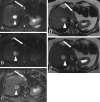

Methods: Seventy-three patients with 215 confirmed FLLs (115 benign, 100 malignant) underwent 1.5-T MRI with respiratory-triggered single-shot SE DWI (b = 50, 400, 800) and dual-echo T2TSE (TR = 3,000 ms; TE1 = 84 ms; TE2 = 228 ms). ADC values and T2 relaxation times of FLLs were calculated. Sensitivity, specificity and accuracy of both techniques in diagnosing malignancy were assessed.

Results: The mean ADC value of malignant tumours (1.07 × 10(-3) mm(2)/s) was significantly lower (P < 0.05) than that of benign lesions (1.86 × 10(-3) mm(2)/s ); however, with the use of the optimal cut-off value of 1.25 × 10(-3) mm(2)/s, 20 false positive (FP) and 20 false negative (FN) diagnoses of malignancy were noted, generating 79 % sensitivity, 82.6 % specificity and 80.9 % accuracy. The mean T2 relaxation time of malignant tumours (64.4 ms) was significantly lower (P < 0.05) than that of benign lesions (476.1 ms). At the threshold of 107 ms 22 FP and 1 FN diagnoses were noted; the sensitivity was 99 %, specificity 80.9 % and accuracy 89.3 %.